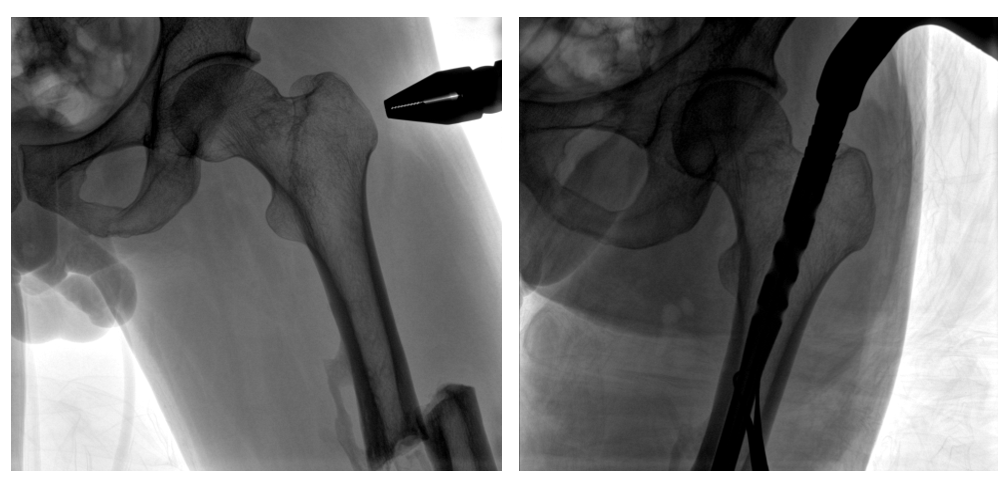

普愛醫(yī)療PLX119C大平板一體式C形臂采用30CM×30CM的平板探測器,在脊柱和長骨骨折等骨科手術(shù)治療中,獲取更大視野、更清晰的骨折部位圖像,能夠有助于醫(yī)生在術(shù)中及時了解和評估骨折部位的對位、對線情況,且能進行長度和角度測量,為進一步提高手術(shù)質(zhì)量提供強有力的支持。